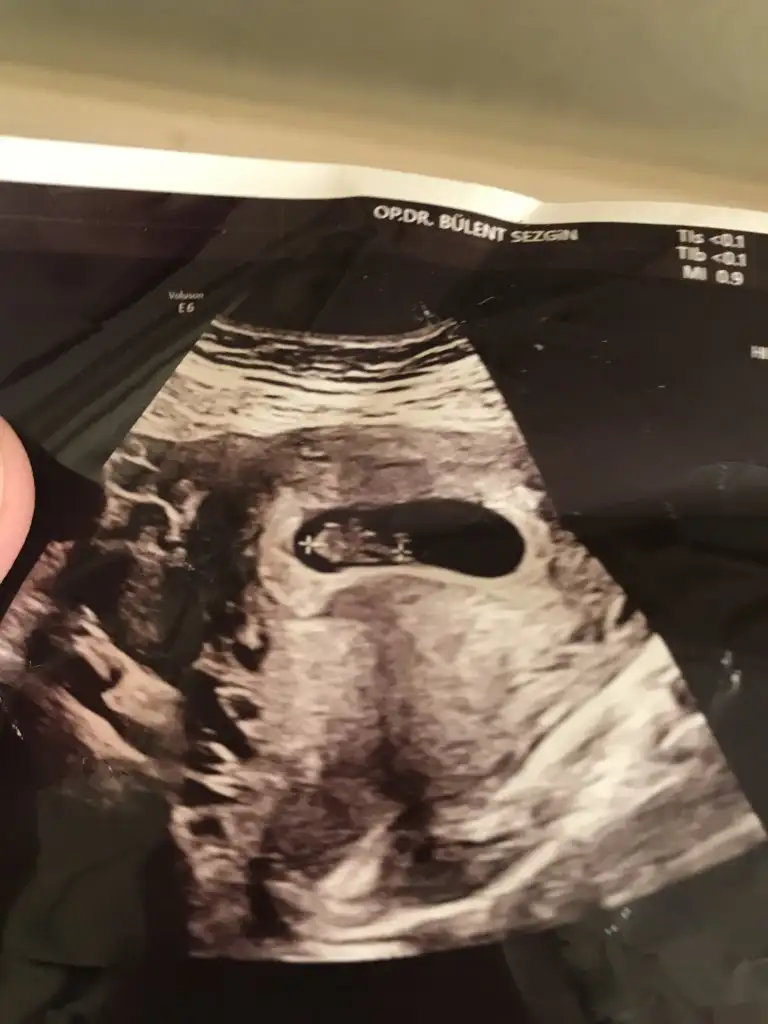

Benimkini de tahmin edebilirsinizErkek ve kız için 11 + 12+ yada 13 hafta usg görüntüsü olmalı açıklamalar asagıda yazıyorrabbim herkesin gönlüne göre nasip etsin inşallah .. ecmain

[/B]Eki Görüntüle 473828 gordugunuz gibi ust taraftaki simgedende anlasildigi gibi eger cikinti paralel ise kiz

yok 30°lik bir aciyla yukari dogru bakiyorsa %99 oglunuz olacak demektir simdi bi kac ornek resimler daha koyacagim kiziminkide dahil

Eki Görüntüle 473831 simdi burada cikintilara bakin eger bel popo cizgisine paralel ise kiz

yok 30 derecelik bir aciyla yukari bakiyorsa erkek

Kız görünüyorKızlar hiç anlamıyorum şu nub işlerinden bana da bakarmısınız 12+2 ultrason resimleri doktor hiç birşey söylemedi tahmin var mı